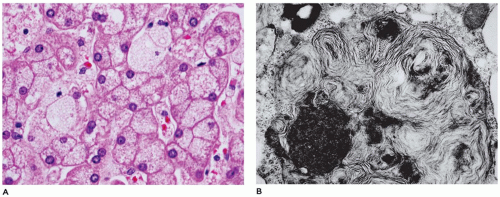

Болезнь Нимана-Пика Тип А: Симптомы и лечение

Раздел: Визуальный дайджест